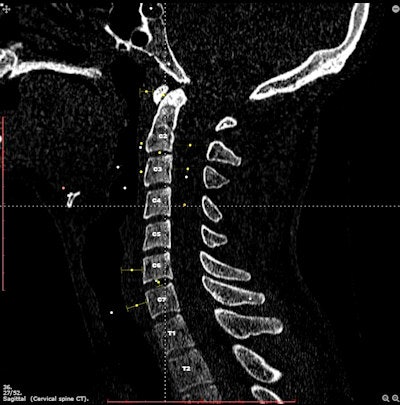

The modern radiologist works on PACS workstations in their clinical practice. So why not use a workstation-like interface to learn many of the crucial skills needed to be a radiologist? That's the theory behind Imaging Anatomy, an interactive online atlas developed by Danish radiology resident Dr. Jens Borgbjerg.

The open-access atlas is designed to assist users in developing skills for navigating volumetric datasets, said Borgbjerg of Aalborg University Hospital. Radiological anatomical structures are identified and presented in multiple planes, with an interface that functions just like a PACS workstation.

What's more, users can gain understanding of how the presentation of anatomy is affected by image manipulation tools such as zoom, pan, brightness/contrast adjustment, CT window/level selection, and caliper/angle measurement, he said.

"The idea is that such an atlas can provide familiarization with anatomy in a form that mimics the way you typically work with anatomy in modern clinical environments, and allows for assimilation of this familiarization into clinical practice," Borgbjerg told AuntMinnieEurope.com.

The imaging studies found on Imaging Anatomy were acquired from Aalborg University Hospital's PACS database and were anonymized prior to use on the site, which was launched in June 2014. He shared more details on Imaging Anatomy in a poster presentation at the 2015 ECR.

Imaging Anatomy is being utilized around the world. So far in September, the site has been visited by users from 114 countries, he said. It has 23 anatomical modules and includes x-ray, CT, MRI, and ultrasound images.